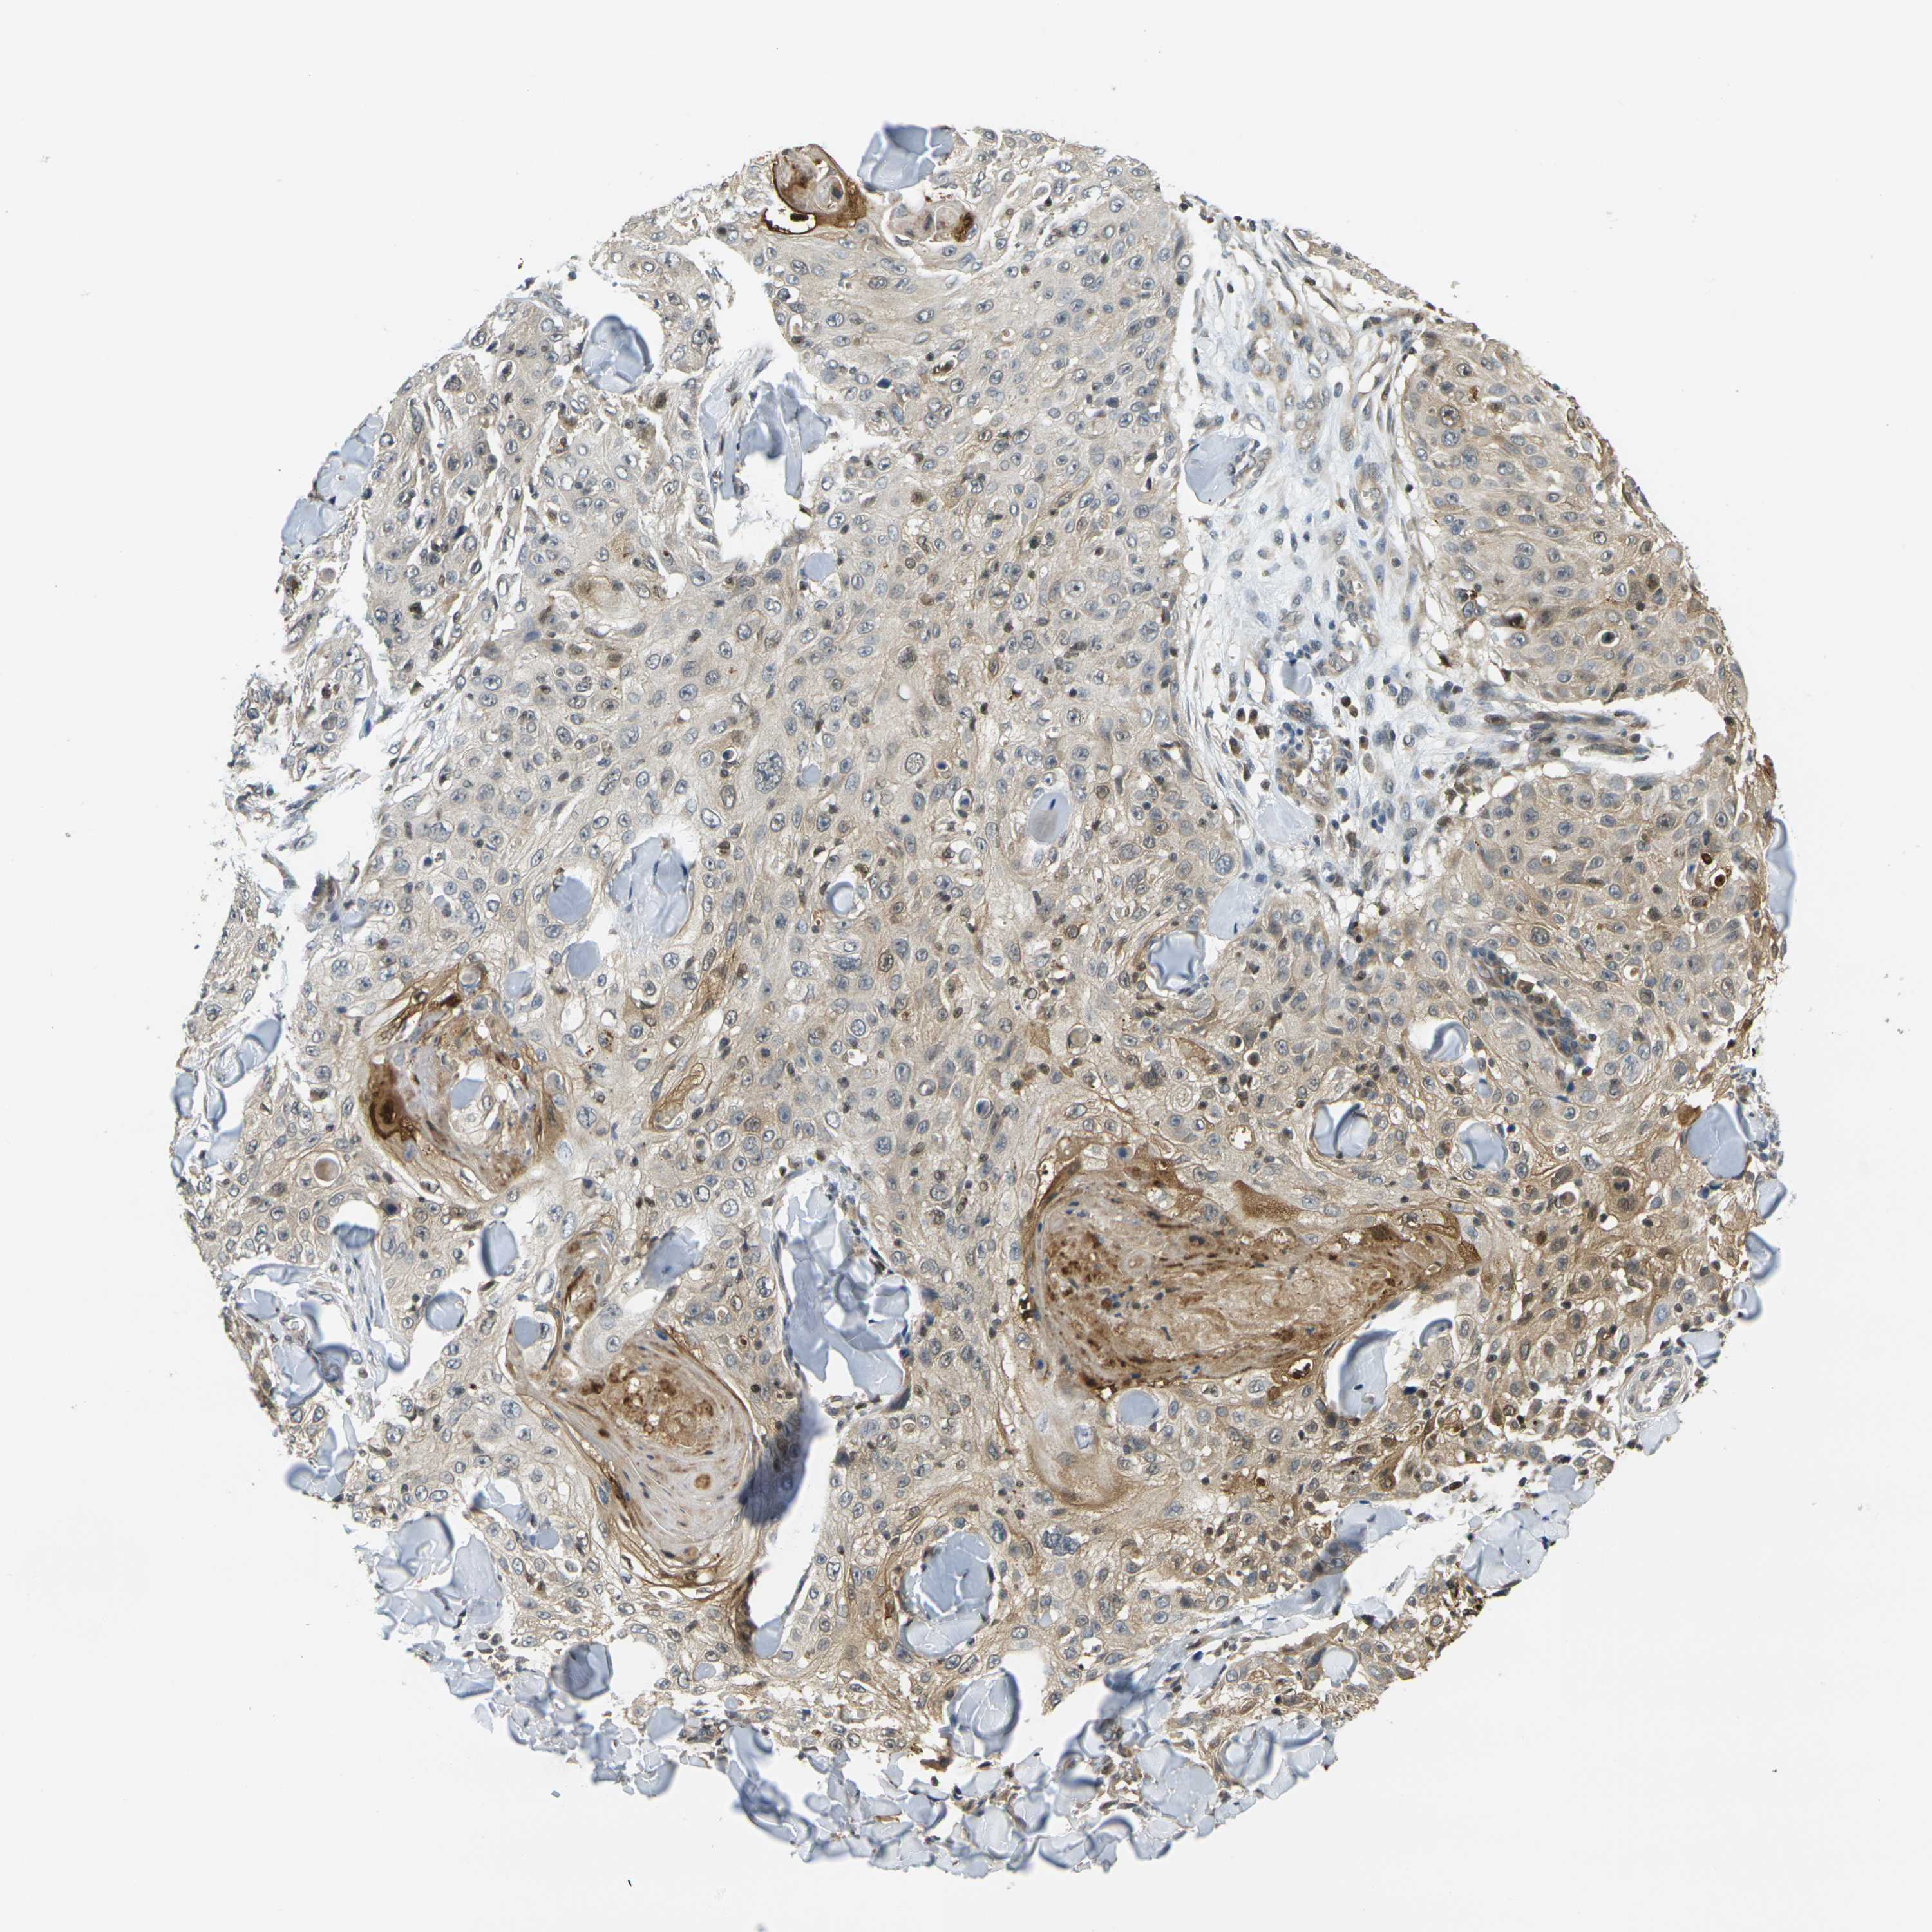

SKIN CANCER - Protein expressioni

A mouse-over function shows sample information and annotation data. Click on an image to view it in a full screen mode. Samples can be filtered based on level of antibody staining by selecting one or several of the following categories: high, medium, low and not detected. The assay and annotation is described here.

Each image is clickable and will lead to virtual microscopy that enables deeper exploration of all samples and also displays staining intensity scores, fraction scores and subcellular localization as well as patient and tissue information for each sample.

Antibody HPA013856

Antibody HPA017762

Squamous cell carcinoma, NOS

Basal cell carcinoma

Squamous cell carcinoma in situ, NOS

Squamous cell carcinoma, metastatic, NOS